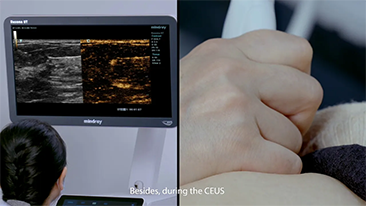

Aparaty ultrasonograficzne z serii Resona, dzi?ki szerokiej gamie za pomoc? wszechstronnych sond do r√≥?nych zastosowaŇĄ i wydajnych narz?dzi do zastosowaŇĄ klinicznych, pomagaj? U?ytkownikom stawia? dok?adniejsz? i efektywniejsz? diagnoz? oraz ocenia? wyniki.

Produkty do obrazowania ogólnego